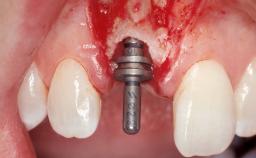

Immediate Flapless Placement of an Implant in a Maxillary Right Lateral Incisor Site

This 43-year-old male patient, a non-smoker, came to our practice because of a fracture of tooth 12 caused by a bicycle accident. Due to the combined para- and infrabony crown and root fracture, tooth extraction, and subsequent implant placement were suggested to the patient as the therapy of choice. The patient had high esthetic expectations with regard to the treatment outcome and asked for an immediate fixed provisional restoration. His individual esthetic risk profile summed up to a medium esthetic risk.

Placement Protocol Immediate implant placement

Socket Morphology Single-root socket

Socket Integrity Sufficient, with intact bone walls

Bone Volume Sufficient, with intact walls

Loading Protocol Immediate